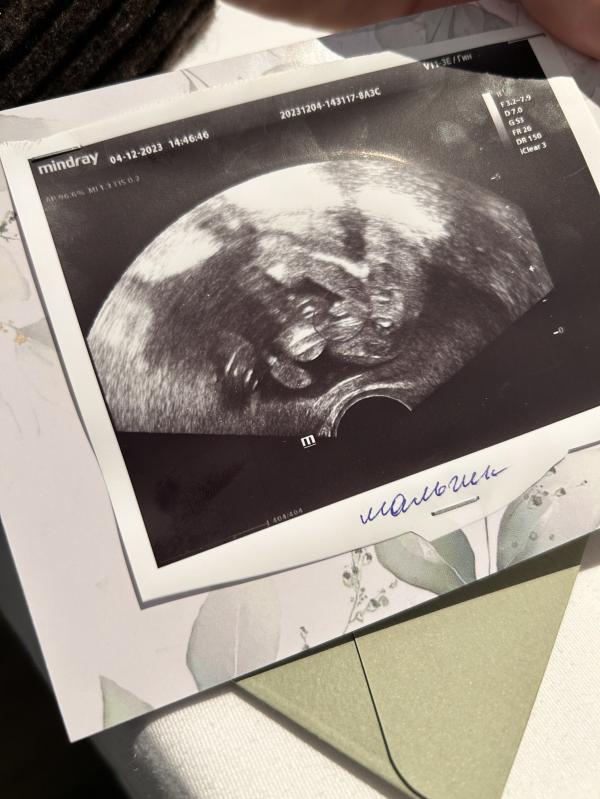

Очень хорошо видно. Это вид снизу, попа, ножки и всё что положено между ними, на втором фото понятнее)

Прекрасно видно причендал🤣🤣🤣снимок снизу. Он у вас сидит на попе, это если бы его на сканер посадили вот сканер вышел бы так😁попа,в разные стороны ноги и между ними мужская принадлежность,поздравляю😊😊😊

Очень даже видно, что мальчик. Вид на попу снизу: ножка, вторая ножка и между ними огуречик.